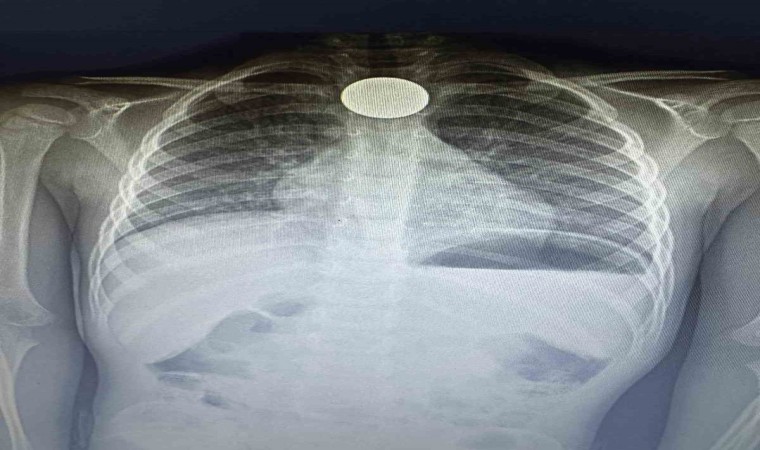

Dik durması hayatını kurtardı

Çekilen röntgende paranın boğazda dik olarak kaldığı görüldü. Doktorlar, paranın yan yatması durumunda küçük çocuğun nefes almasına engel olabileceği ve nefessiz kalarak hayati risk oluşturabileceği aileye anlatıldı. Yapılan 4 saatlik operasyonun ardından para boğazdan çıkarılırken, küçük çocuk ertesi gün taburcu edildi.